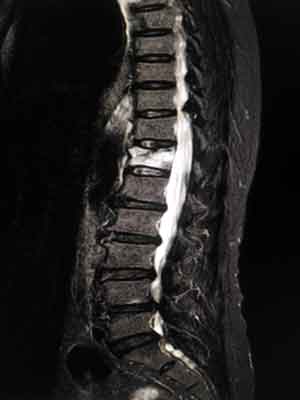

The x-ray image of the spine below shows a compression fracture. The white vertebra is compressed. This can cause a loss of height of the vertebrae.

What has happened is that there’s been so many forces that the disc is actually starting to push through the vertebrae. The vertebrae itself is actually quite a bit shorter in stature than the vertebrae above and below it. It has just compressed in on itself.

compression fracture melioguide physiotherapy ottawa